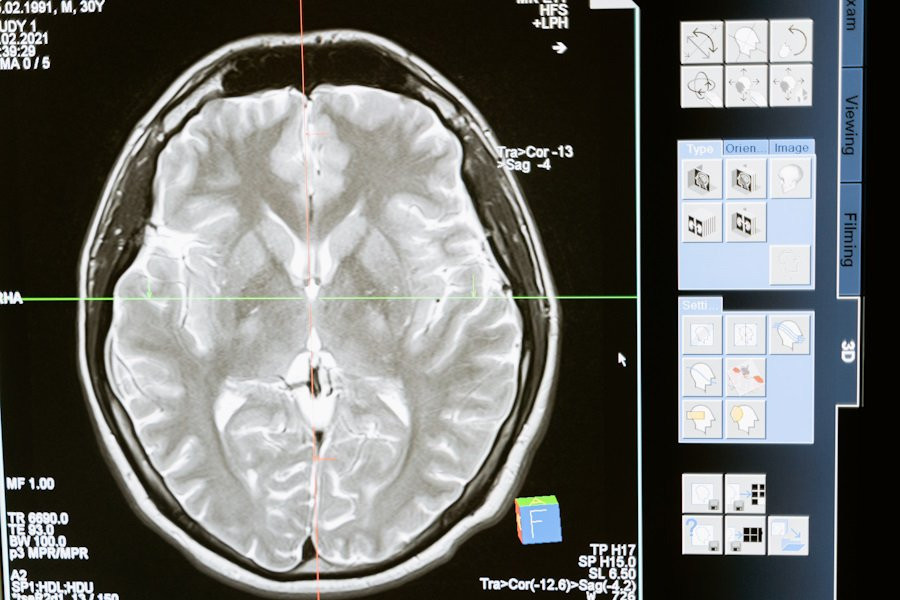

Ученые сделали важный шаг в понимании того, как мозг интегрирует информацию во время сложных когнитивных процессов, таких как чтение. В новом исследовании, проведенном в University of California, было обнаружено, что нейроны в различных областях мозга синхронизируются, когда человек читает и принимает семантические решения.

Результаты этого исследования опубликованы на портале Nature. Исследователи использовали внутричерепную электроэнцефалографию (ЭЭГ) для наблюдения за активностью мозга у участников эксперимента.

Основное открытие заключается в том, что высокочастотные колебания (~90 Гц) в нейронах синхронизируются с высокой точностью, когда мозг объединяет информацию из разных областей во время чтения. Эти ко-пульсации, или синхронизированные всплески активности, усиливаются в момент, когда мозг связывает визуальную информацию со смыслом и формирует осознанное понимание прочитанного.